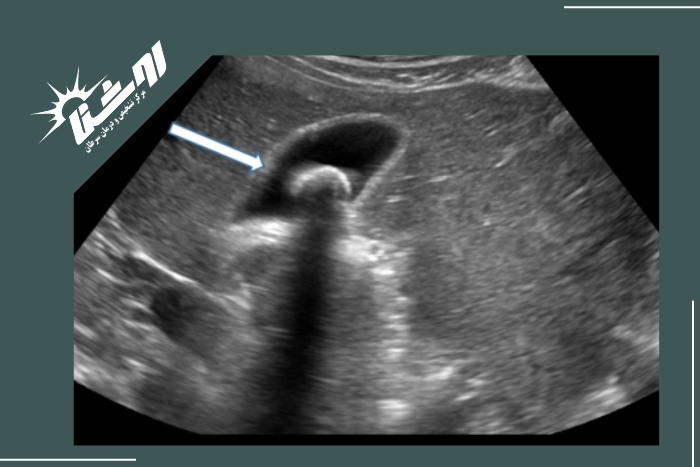

سنگهای صفراوی معمولاً به شکل نقاط روشن در اولتراسوند دیده میشوند. این سنگها سایهای تیره در پشت خود ایجاد میکنند که به تشخیص آنها کمک میکند. حتی سنگهای کوچک نیز معمولاً قابل شناسایی هستند.بررسی دیواره کیسه صفرا

تشخیص سنگ کیسه صفرا با سونوگرافی